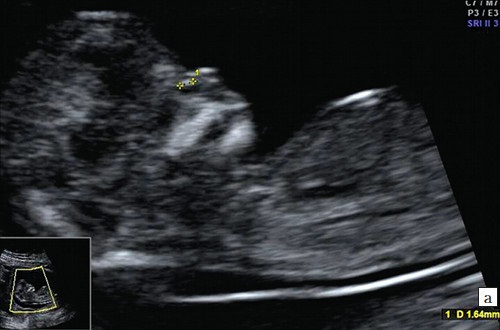

Показатели нормы УЗИ – исследования

Пренатальный скрининг считается безвредным для матери и ребенка. Сравнение полученных показателей с нормативами дает наиболее полную картину состояния и рисков беременности.

Основные показатели:

- КТР (копчико – теменной размер). Дина плода от темени до копчика должна составлять от 43 до 85 мм. Уменьшение длины плода говорит о замедленном развитии, или генетической патологии.

- БПР (бипариетальный размер). Определяется расстоянием от виска до виска. Изменения данных БПР говорят о патологиях головного мозга.

- ТВП (толщина воротникового пространства). Повышенный показатель требует углубленного анализа на выявление синдрома Дауна, Эдвардса.

- Длина кости носа. Показатели исследования варьируются от анатомических особенностей строения до генетических патологий.

- ЧСС (частота сердечных сокращений). Заметное урежение или учащение сердцебиения свидетельствует о возможных нарушениях работы головного мозга, пороках внутренних органов.

- Размер хориона, амниона и желточного мешка. На первом этапе развития плода они являются основой плаценты, необходимой для нормального вынашивания беременности. Неправильное местоположение хориона грозит выкидышем. Показатели амниона необходимы для изучения околоплодных вод. Желточный мешок – питательная среда для развития внутренних органов. Его отсутствие или минимальное наличие свидетельствует о динамике развития беременности.

Частота сердечных сокращений

Частота сердечных сокращений у здорового плода должна соответствовать нормам его развития. Этот показатель считается корректным только при условии, что размеры плода по КТР (кокцигиально-теменной размер) составляют не менее 8 мм. В противном случае говорить о нормальных значениях ЧСС не следует. В процессе роста плода частота сердечных сокращений постепенно уменьшается.

На 9-10 неделе беременности сердцебиение может достигать 170-190 ударов в минуту, однако к 13 неделе этот показатель снижается до 160 ударов. Небольшие колебания в этих значениях считаются физиологическими и не представляют угрозы. Если же сердцебиение отсутствует, это может указывать на замершую беременность. Для подтверждения или опровержения данного диагноза необходимо провести повторное УЗИ и дополнительные исследования.

Снижение ЧСС до менее 100 ударов в минуту может указывать на синдром Эдвардса.

Увеличение частоты сердечных сокращений до 200 ударов в минуту является тревожным признаком, который может свидетельствовать о синдроме Патау. Однако маркеры ЧСС не являются основными для диагностики хромосомных заболеваний; они лишь указывают на возможные риски развития патологий. Комплексный мониторинг всех органов и систем необходим для составления полного прогноза беременности.

Бипариентальный размер

Бипариентальный размер означает цифровые показатели ширины головы плода от виска до виска. БПР является основным показателем развития головного мозга будущего ребенка.

Показатели также могут служить основанием для уточнения срока беременности и, в некоторых случаях, определения способа физиологических родов. При крупных размерах головки ребенка может встать вопрос о плановом кесаревом сечении.

Норма БПР на 11 – 13 неделе развития должна находиться в пределах от 13 до 28 мм. Выход за пределы нормы допускается, при условии пропорционального увеличения всех показателей – КТР, ТВП, носовой кости. Это указывает на крупный размер плода. Слегка завышенный БПР, при соответствии норме остальных маркеров, выравнивается к концу 14 недели.

Заметное повышение показателя свидетельствует о наличии патологий головного мозга, несовместимых с жизнью.

Минимальные размеры БПР указывают на недоразвитие полушарий или отсутствию сегментов головного мозга. Тяжелые пороки развития не поддаются лечению, перинатальный прогноз неблагоприятный. Выбор о прерывании или оставлении беременности женщина делает самостоятельно.